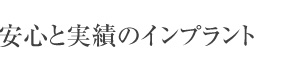

| ガイドを使用した実際のインプラント埋入手術 | 術前の3Dシミュレーション画像 |

ノーベルガイドを使用した実際のインプラント埋入症例。手術中の様子、術前の3Dシミュレーション画像、インプラント埋入手術後のCT画像です。 手術前後の2つの画像を合わせてみるとほぼ完全に一致します。これがノーベルガイドが現在最も安全で正確なインプラントシステムであると言われる理由です。 |

埋入後のレントゲン。

左上にもサイナスリフト(上顎の骨量を増やす治療)と同時に 2本のインプラントを埋入しました。 |